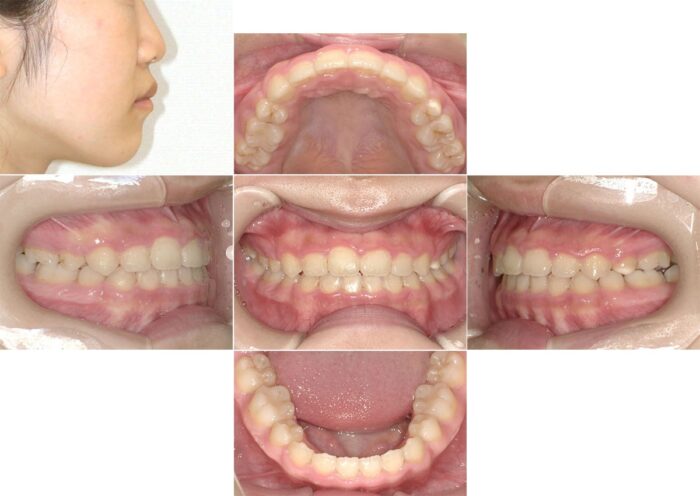

歯を抜いたことで横顔の変化が大きく、気にされていた口元の突出が解消されました。

マウスピースと部分的にワイヤー矯正を併用した症例

部分的にワイヤー矯正をつけてマウスピースとワイヤー矯正を併用して治療を進めることもあります。

前歯のすきっ歯の改善と目立たない矯正装置を希望され、マウスピース矯正装置(インビザライン)で治療を始めました。ところが、治療開始5ヶ月を過ぎた頃から、大学生になり環境の変化で、通院間隔が9ヶ月間も空いてしまいました。

そのため、マウスピースが合わなくなってしまい、ワイヤー矯正へ変更の提案をしましたが、目立つ装置は避けたいということで奥歯だけワイヤー矯正をつけて補正することになりました。

7ヶ月間、装置を併用した治療を行い、その後マウスピースのみで細かい微調整とかみ合わせの調整を行いました。通院間隔が空いてしまったこと以外は問題なく治療が進み、すきっ歯が改善されました。

【症例詳細】

- 主訴:すきっ歯が気になる

- 診断名:空隙歯列・過蓋咬合

- 初診時年齢:17歳・女性

- 使用装置:マウスピース矯正装置(インビザライン)・表側ワイヤー矯正

- 抜歯部位:上顎左右犬歯・上顎左側第二小臼歯(欠損)、上顎右側乳犬歯

- 治療期間:3年6ヵ月

- 費用:865,000円(税込951,500円)

- リスクと副作用:痛み、歯根吸収、歯肉退縮、むし歯、後戻り